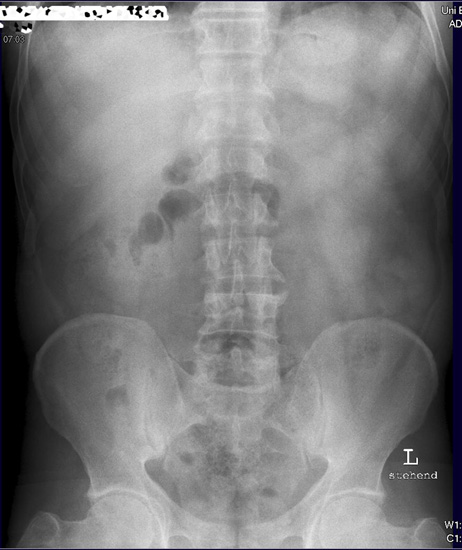

Abdomen im Stehen

Fehler

Diese Aufnahme ist nicht genügend aussagekräftig, da die Zwerchfelle nicht komplett abgebildet sind. Bei Frage freie Luft sollten immer die Zwerchfelle im Stehen zu stehen sein.

Abhilfe

Solch eine Aufnahme müsste noch mal wiederholt werden und etwas höher eingestellt werden. Viele Patienten können auf Grund ihrer abdominellen Beschwerden nicht tief genug einatmen. Deshalb nicht blind abdrücken, sondern genau zum Patienten schauen wie er einatmet, und nicht zu knapp nach oben hin einstellen.